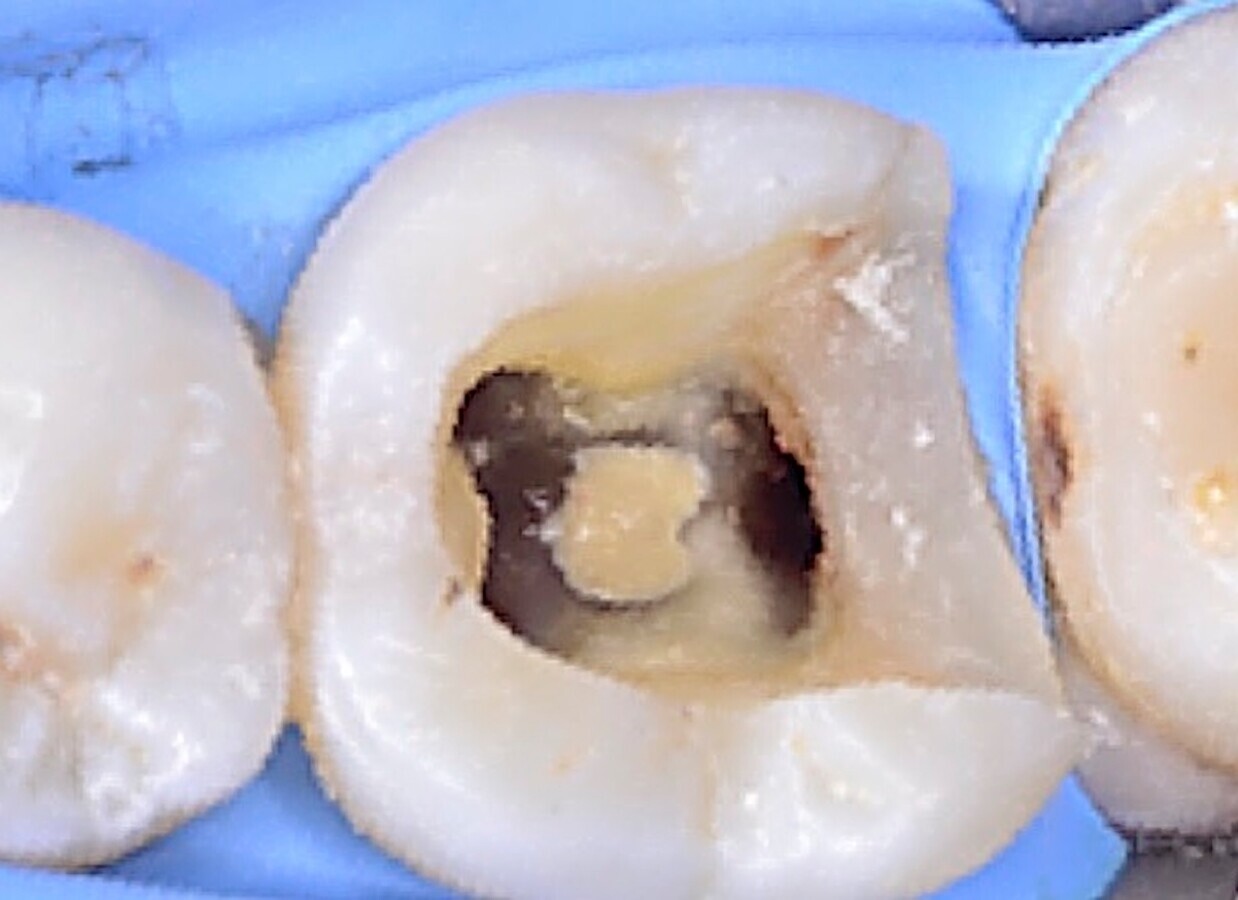

Fig. 4. Imagen clínica donde se puede apreciar la perforación en furca.